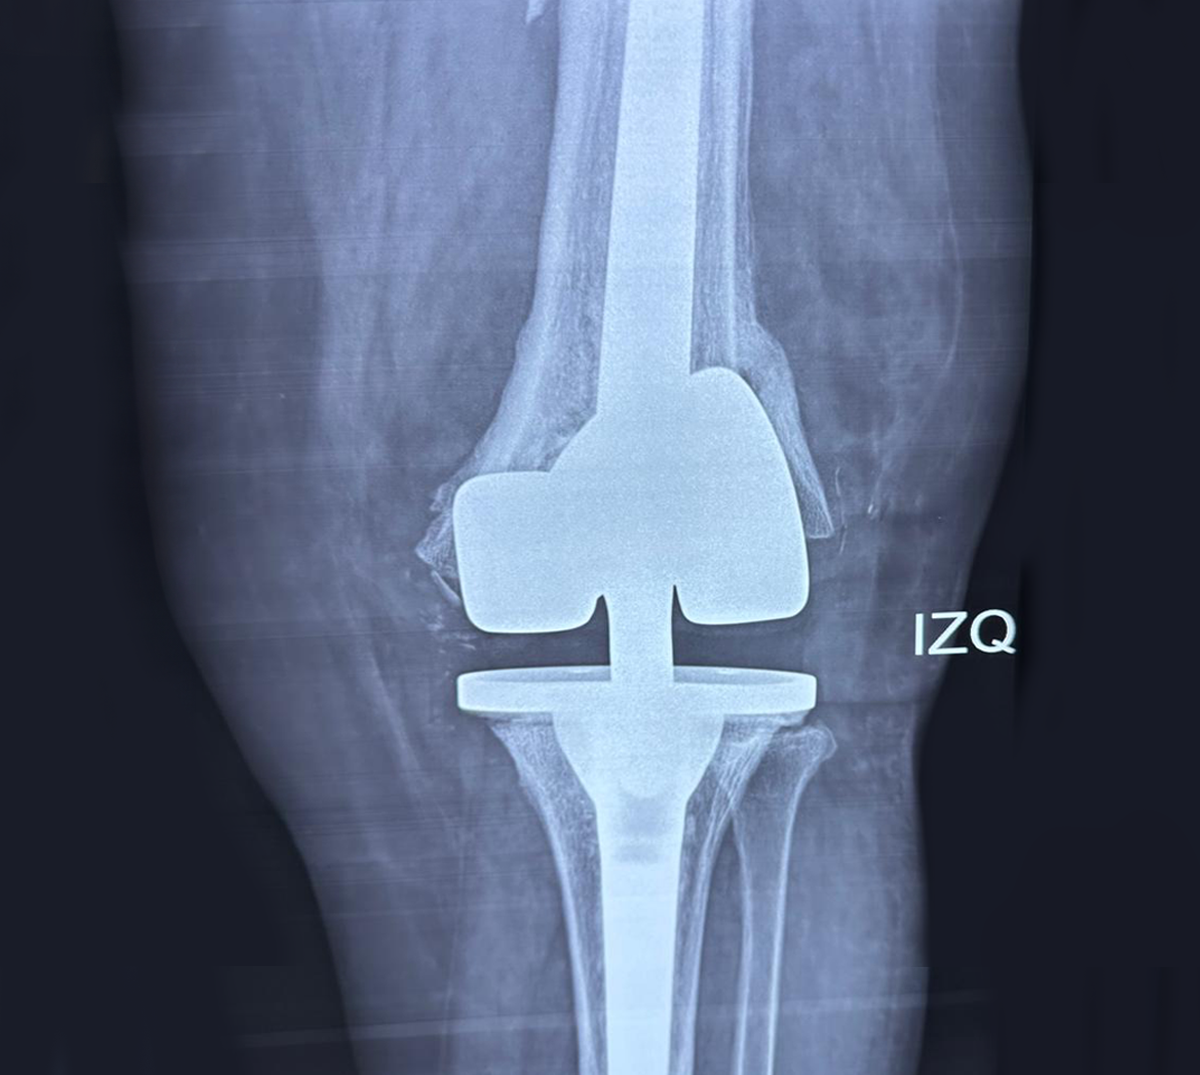

REEMPLAZO ARTICULAR

(HOMBRO, RODILLA Y CADERA)

Las prótesis son implantes ortopédicos que se colocan en el cuerpo con la finalidad de sustituir a una articulación lesionada.

De forma común, sus indicaciones son por secuelas de osteoartrosis, artritis reumatoide y fracturas en algunos casos.